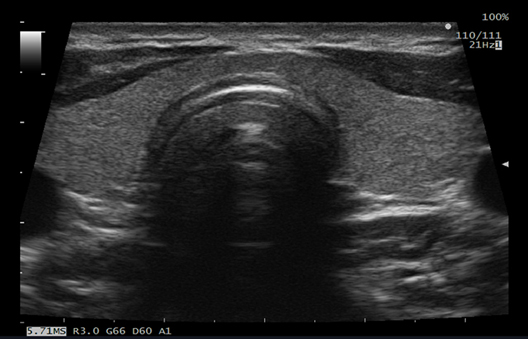

Ofrece un campo de visión más amplio al escanear con transductores lineales, lo que mejora la visualización de los vasos, órganos y tejidos que los rodean.

Mide automáticamente los valores máximos y medios del grosor íntima-media (IMT) después de la colocación de una región de interés (Region of Interest, ROI) en la vista de eje largo de la arteria carótida. Debido a que se calcula a partir de todos los puntos en el rango especificado, se puede esperar una mejora en la precisión.